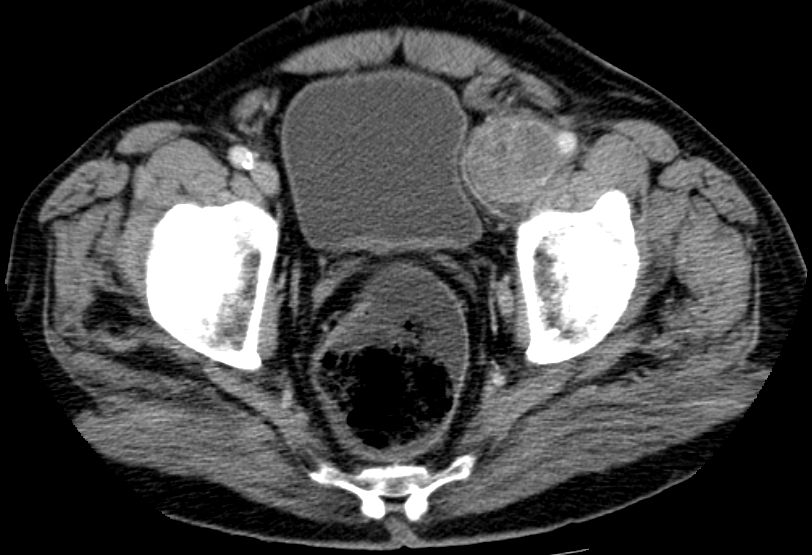

| Leiste | 72-jähriger Landwirt mit einem Leiomyosarkom der linken Leiste pT2b pN0 G2 R0. 110 x 50 x 50 mm großer, solider Tumor mit enger Lagebeziehung zum Gefäßbündel.

Infiltration des Musculus rektus abdominis.![]() |